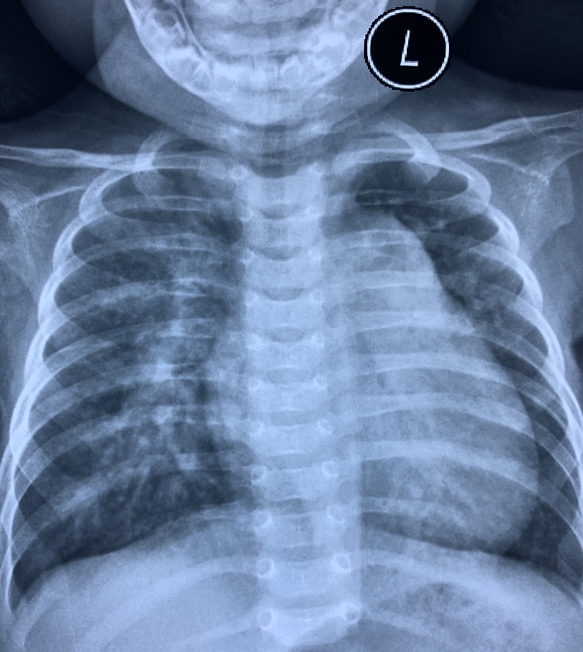

Phim chụp ngực bệnh nhi trước và sau ca phẫu thuật. Ảnh: BVCC. |

Bệnh nhi được gây mê toàn thân, mổ mở qua đường xương ức. Sau đó, phẫu thuật viên sử dụng dù để bít lỗ thông liên thất. Kết thúc ca mổ, các bác sĩ chụp buồng tim và siêu âm tim, tháo dụng cụ, dây dẫn. Bước cuối cùng, đội ngũ y tế cầm máu và đóng xương ức.

Giai đoạn hậu phẫu gây nhiều khó khăn cho các bác sĩ do T. bị tăng áp lực động mạch phổi và suy dinh dưỡng. 7 ngày sau, T. được rút máy thở. 2 tuần tiếp theo, bé xuất viện.